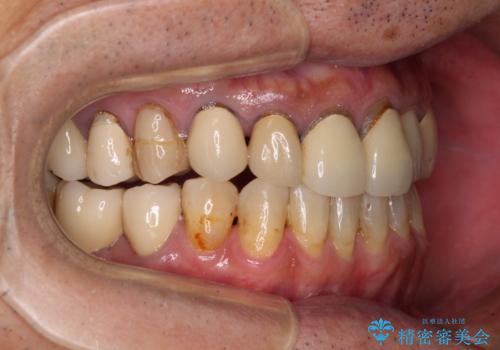

奥歯1歯分を動かすには時間がかかるため、矯正治療には思いの外時間がかかりました。

痛みのある奥歯は必要に応じて根管治療を行い、左下インプラントは角化歯肉の移植により清掃性を向上させ、気になっていた部分をしっかりと改善させることができました。